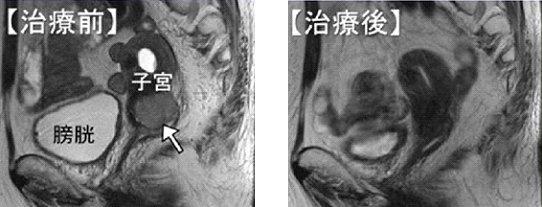

- 子宮頸癌に対する外照射を併用したRALS前後のMRI所見

- 治療前に見られた子宮頸部の腫瘍(矢印)は治療後に消失している。